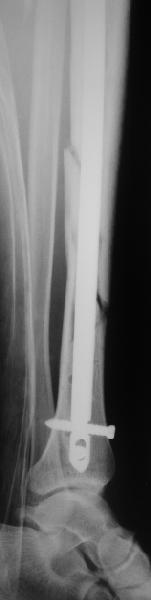

[Ortho] неправильно фиксированный перелом

Все наши сомнения связаны с тем, что этих незначительных погрешностей

(небольшой вальгус, неглубоко пробит гвоздь, мало запирающих винтов в

дистальном отломке) не одна, а несколько и вместе они могут

значительно осложнить дальнейшую жизнь пациенту. В нашей практике были

подобные случаи, при которых после разрешения полной нагрузки либо

начинала увеличиваться деформация, либо происходил перелом гвоздя по

ближайшему отверстию. Кроме того, при диафизарных переломах,  имея в

арсенале надежный фиксатор, нет никакой необходимости вынуждать

пациента ограничивать нагрузку на ногу в течении 2-3 месяцев.

Взвесив все <<за>> и <<против>> мы приняли решение и выполнили

реостеостинтез: выбили гвоздь до линии перелома, провели отклоняющую

спицу, забили обратно гвоздь и заблокировали внизу 3-мя винтами,

вверху одним. Вся операция заняла меньше часа. Сегодня пациент ушел от

нас домой с полной нагрузкой на ногу.